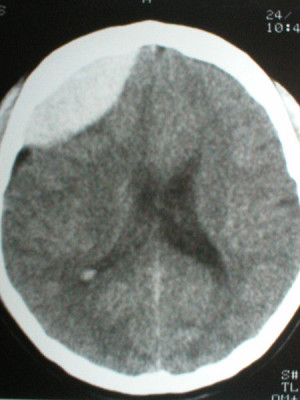

.

Casos Neuroloquirúrgicos

Envíado por Dr. Ruben Eduardo Amaya Contreras